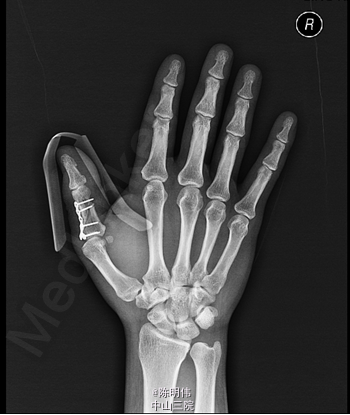

入院后完善相关检查,无明显手术禁忌,行右拇指近节指骨骨折切开复位内固定术,术程顺利,术后镇痛、改善循环治疗,并加强手术伤口换药。

患者挤压伤,能够尽早手术对患指的恢复非常重要。该患者行钢板固定术后影像不错,为何不考虑克氏钉固定呢

患者受伤机制明确,X线骨折移位明显,内固定术处理得很好,要注意术后康复恢复。